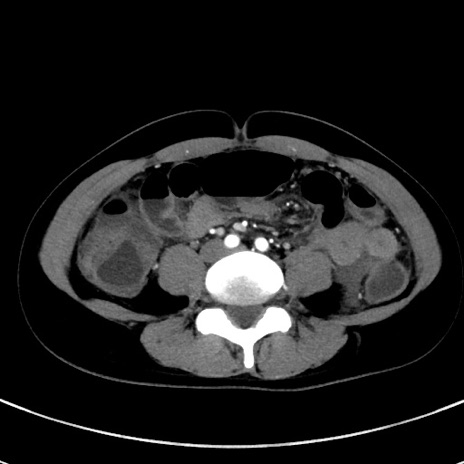

冠状断像

【症例】20歳代女性

【主訴】嘔吐、下腹部痛

【現病歴】昨日夕食後に嘔吐し下腹部痛が出現。本日になっても嘔吐持続し改善しないため来院。

【身体所見】意識清明、BT 37.2℃、BP 108/67mmHg、腹部:平坦、やや硬、下腹部正中から右にかけて圧痛あり、反跳痛軽度あり、tapping pain(+)。

【データ】WBC 13600、CRP 14.94